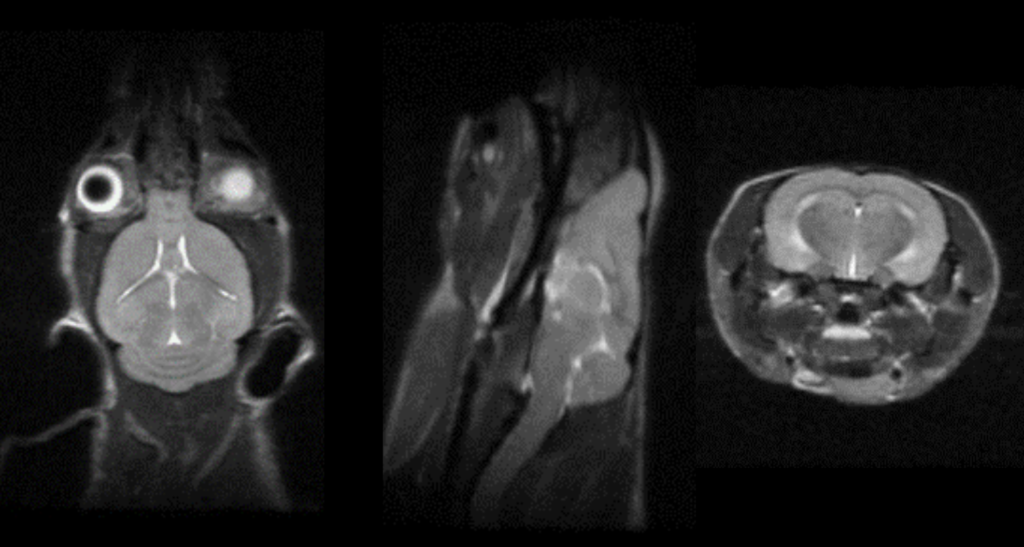

In a recent paper entitled “Treatment of Ischemic Stroke by Atorvastatin-loaded PEGylated Liposome” researchers at Chonnam National University Medical School and Hwasun Hospital demonstrated that PEGylated liposomes loaded with atorvastatin (LipoStatin) efficiently accumulated at the site of cerebral ischemic injury. Images obtained using the Aspect Imaging M7 preclinical MRI and the Sedecal SuperArgus preclinical PET/CT system showed reduced infarct volume (anatomical MRI), improved neurological function recovery, and improved brain metabolism, as demonstrated by a significantly increased uptake of the clinically-used radiotracer 18F-Fluoro-deoxyglucose (FDG). Ex vivo examination of the rate brain at study endpoint showed that treatment with lipoStatin led to significant anti-inflammatory effects and recovery of blood-brain barrier breakdown and endothelial dysfunction, as demonstrated by reduced extravasation of evans blue measured by ex vivo fluorescence imaging system, like the Vilber Newton bioluminescence and fluorescence system.